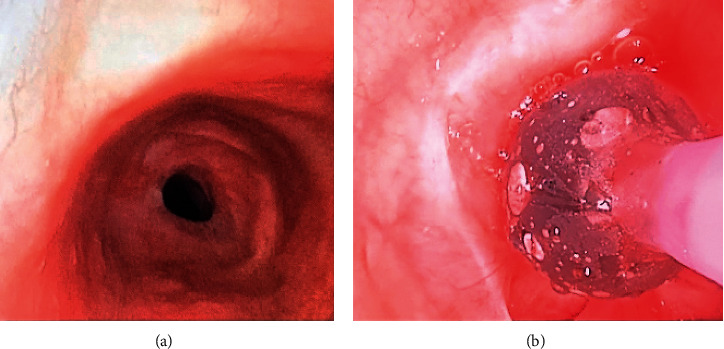

声门下气管狭窄可在长时间插管或气管切开术后发生。这种狭窄可能会变得严重,并导致难以通过内镜干预进行气管切除的症状。由于气道解剖、生理和与外科团队共享气道管理,该手术呈现独特的麻醉问题。我们报告一名68岁的患者,尽管球囊扩张并使用氧气和螺旋手术治疗,但由于症状持续存在,接受了颈椎气管切除术和重建。我们的麻醉管理涉及多种技术,以确保手术安全完成。首先,我们使用4号Ambu®AuraStraight™(丹麦)声门上气道装置和柔性支气管镜进行气道管理,以便在气管内插管(ETT)放置前定位狭窄和扩张。该内镜评估阶段的常规方法是使用刚性支气管镜检查。其次,我们使用先前的CT图像来帮助指导我们选择ETT管的尺寸。第三,我们在大部分手术过程中使用全静脉麻醉,因为完成气管切除术需要间歇性呼吸暂停。最后,拔管必须非常小心地进行,以尽量减少患者过度的颈部运动,避免任何重新插管。这两种情况都可能导致气管重建的灾难。

Subglottic tracheal stenosis can occur after prolonged intubation or tracheostomy. This stenosis can become severe and causes symptoms refractory to endoscopic interventions that require tracheal resection. This surgery presents unique anesthetic issues due to the airway anatomy, physiology, and shared airway management with the surgical team. We present the case of a 68-year-old patient who underwent cervical tracheal resection and reconstruction due to persistent symptoms despite balloon dilation and medical management with oxygen and heliox. Our anesthesia management involved several techniques that allowed the safe completion of this procedure. Firstly, we started the airway management with a combined size 4 Ambu® AuraStraight™ (Denmark) supraglottic airway device and flexible bronchoscopy to allow localization of the stenosis and dilation before endotracheal tube (ETT) placement. The conventional approach for this endoscopic evaluation phase is to use rigid bronchoscopy. Secondly, we used prior CT images to help guide our ETT tube size selection. Thirdly, we used total intravenous anesthesia during most of the procedure because of the intermittent apnea necessary to complete the tracheal resection. Lastly, extubation had to be done very carefully to minimize excessive patient neck movement and avoid any reintubation. Both could lead to a catastrophe with the newly reconstructed trachea.